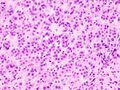

علم الانسجة

يشير تحليل النسيجي المرضي المجهري لعينات الأنسجة التي تم الحصول عليها من قشرة الغدة الكظرية للأفراد الذين يعانون من أعراض مرتبطة بالورم الغدي مثل الالدوسترونية الأولية (PA) إلى أن خلايا الورم الغدي أكبر نسبيًا مع اختلاف السيتوبلازم ، وزيادة التباين في الحجم النووي. يعتمد هذا المؤشر على المقارنة بين عينات أنسجة قشرة الغدة الكظرية السليمة (الطبيعية) والمتأثرة (المرتبطة بالورم الغدي).[بحاجة لمصدر]

يتم تمييز أورام الغدة الكظرية الغدية الأكثر شيوعًا عن سرطان القشرة الكظرية (نظائرها الخبيثة) بواسطة نظام فايس,[11] علي النحو التالي::[12]

| الخصائص[12] | النتيجة |

|---|---|

| درجة نووية عالية (مكبرة ، بيضاوية إلى مفصصة ، ذات حبيبات خشنة إلى كروماتين مفرط اللون ويمكن تمييزها بسهولة ، نوى بارزة))[13] | 1 |

| انقسامات فتيلية أكثر من 5/50 حقول طاقة عالية | 1 |

| انقسامات فتيلية شاذة | 1 |

| السيتوبلازم اليوزيني في> 75٪ من الخلايا السرطانية | 1 |

| بنية منتشرة تزيد عن 33٪ من الورم | 1 |

| نخر | 1 |

| الغزو الوريدي | 1 |

| الغزو الجيبي (لا توجد عضلات ملساء في الجدار) | 1 |

| غزو المحفظة | 1 |

تشير النتيجة الإجمالية إلى:[12]

- 0-2: ورم الغدة الكظرية الغدية

- 3: غير محدد

- 4-9: سرطان القشرة الكظرية